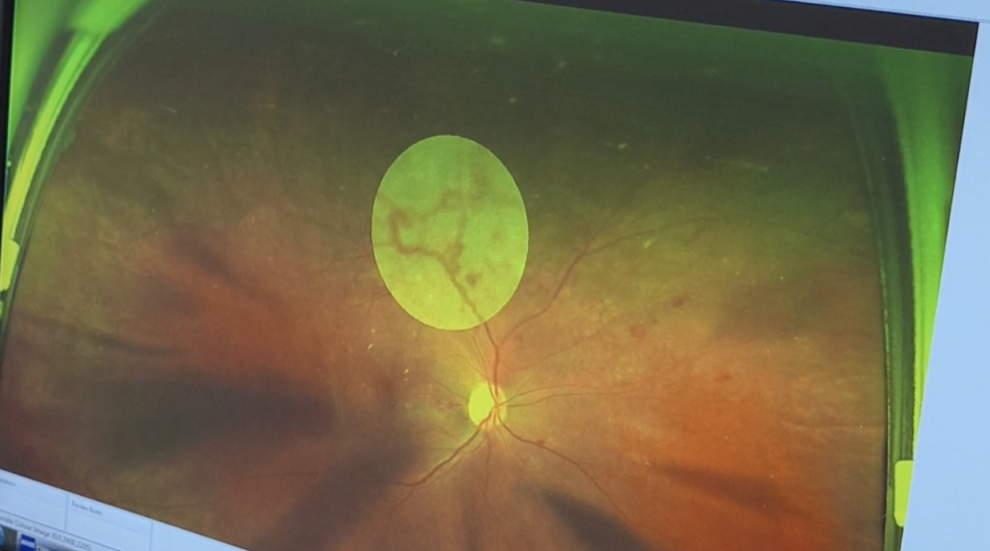

(▲欧堡眼底照相下汪先生眼底新生血管如图所示)

据悉,汪先生(化名)有近20年糖尿病史,此次社区筛查常规体检中,意外发现视网膜新生血管,经岳阳爱尔眼科医院眼底病科主任刘祥明详细检查后,明确该病变的根源是长期控制不佳的糖尿病引发的视网膜病变。值得注意的是,汪先生此前并未出现任何眼部不适症状,完全是通过体检才发现这一潜在致盲隐患。

“眼底新生血管看似是眼部新长出的血管,实则是危害视力的‘隐形杀手’,尤其对于长期患糖尿病的人群,它早期症状极为隐蔽,多数人都是在体检时才发现。”刘祥明主任介绍,这种异常血管的生成多由病理因素诱发,其中糖尿病患者是高发人群。

作为糖尿病三大严重并发症之一,糖尿病性视网膜病变是微血管病变在眼部的典型表现。刘祥明主任解释,汪先生近20年糖尿病史,若血糖长期控制不理想,会导致全身微血管受损,反映在眼部就会出现视网膜微血管障碍,进而诱发新生血管,这也是长期糖尿病患者眼部病变的常见诱因。